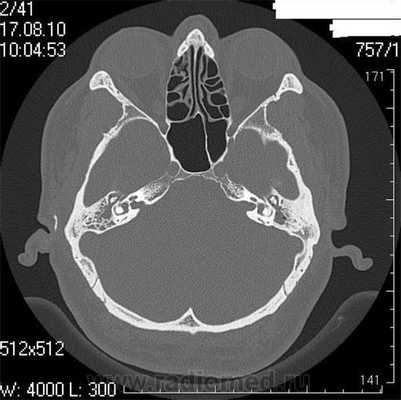

Во время КТ получают послойные снимки височной кости и окружающих тканей в трех плоскостях. Толщина среза составляет всего несколько миллиметров, что позволяет врачу-рентгенологу рассмотреть не только все анатомические образования, но и минимальные патологические изменения.

Снимок (томограмма) височных костей в осевой проекции